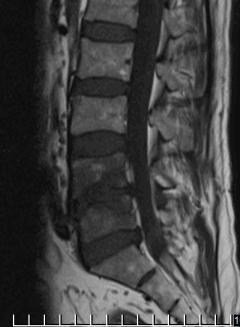

На МРТ в телах VL4-5 сигнал неоднородно снижен. Межтеловая щель сужена. Суставные поверхности неровные с узурацией, с краевыми остеофитами. Мягкие ткани вокруг инфильтрированы, утолщены, абсцессов нет. Спинномозговой канал сужен. За счет протрузии дисков VL4-5, VL5-S1 позвонков. Повышенный сигнал от тел остальных поясничных позвонков.

Рис. 1. МРТ до операции лазерной вапоризации межпозвонкового диска VL4-5